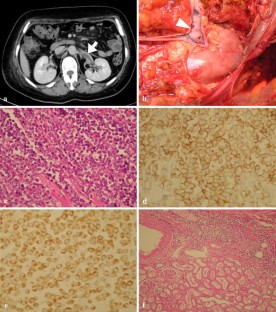

Fig. 1